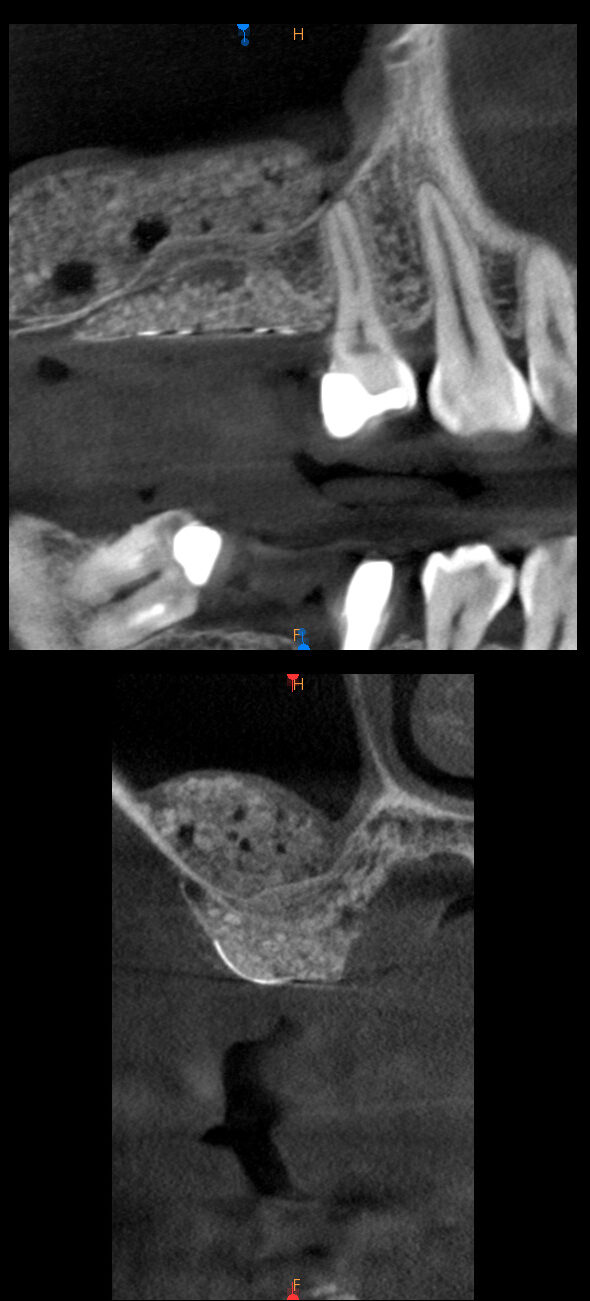

治療後

この失われた部分に、人工骨や再生膜を用いて骨の再生を促す治療です。

インプラント治療の際、インプラントを支えるための骨が不足している場合に行われます。

当院では、生体親和性の高い材料を使用し、感染リスクを抑えた安全な手技で、失われた骨の再生をサポートしています。

骨の再生によって、インプラント治療が可能になり、口腔内の健康を長期的に守ることができます。